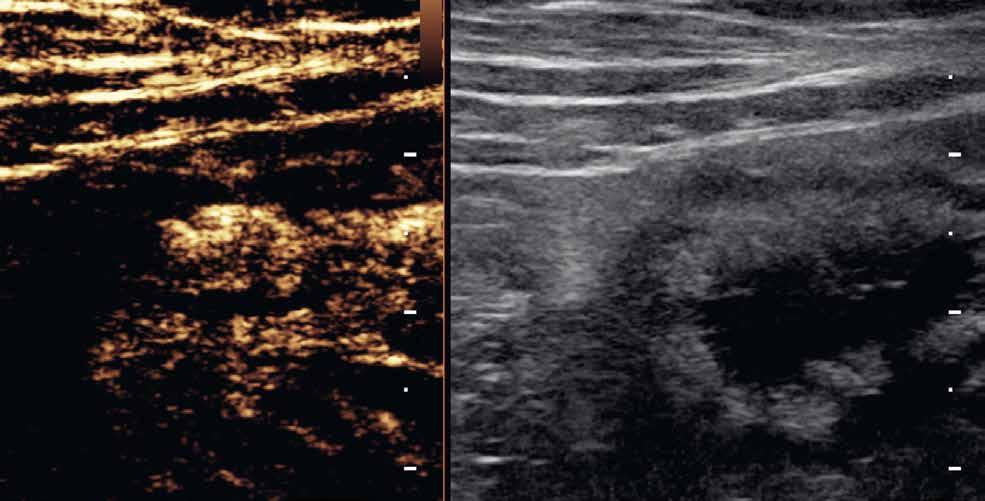

Obr. 1–3: CEUS. Pacient s Crohnovou nemocí ve fázi aktivního zánětu. Po podání kontrastní látky je patrné postupné sycení střevní stěny (1, 2, levá část obrázku), která je výrazně zesílená s akcentovanou hypoechogenní sliznicí (1, 2, pravá část obrázku). Křivka sycení pak svědčí rovněž pro akutní fázi zánětu (3).